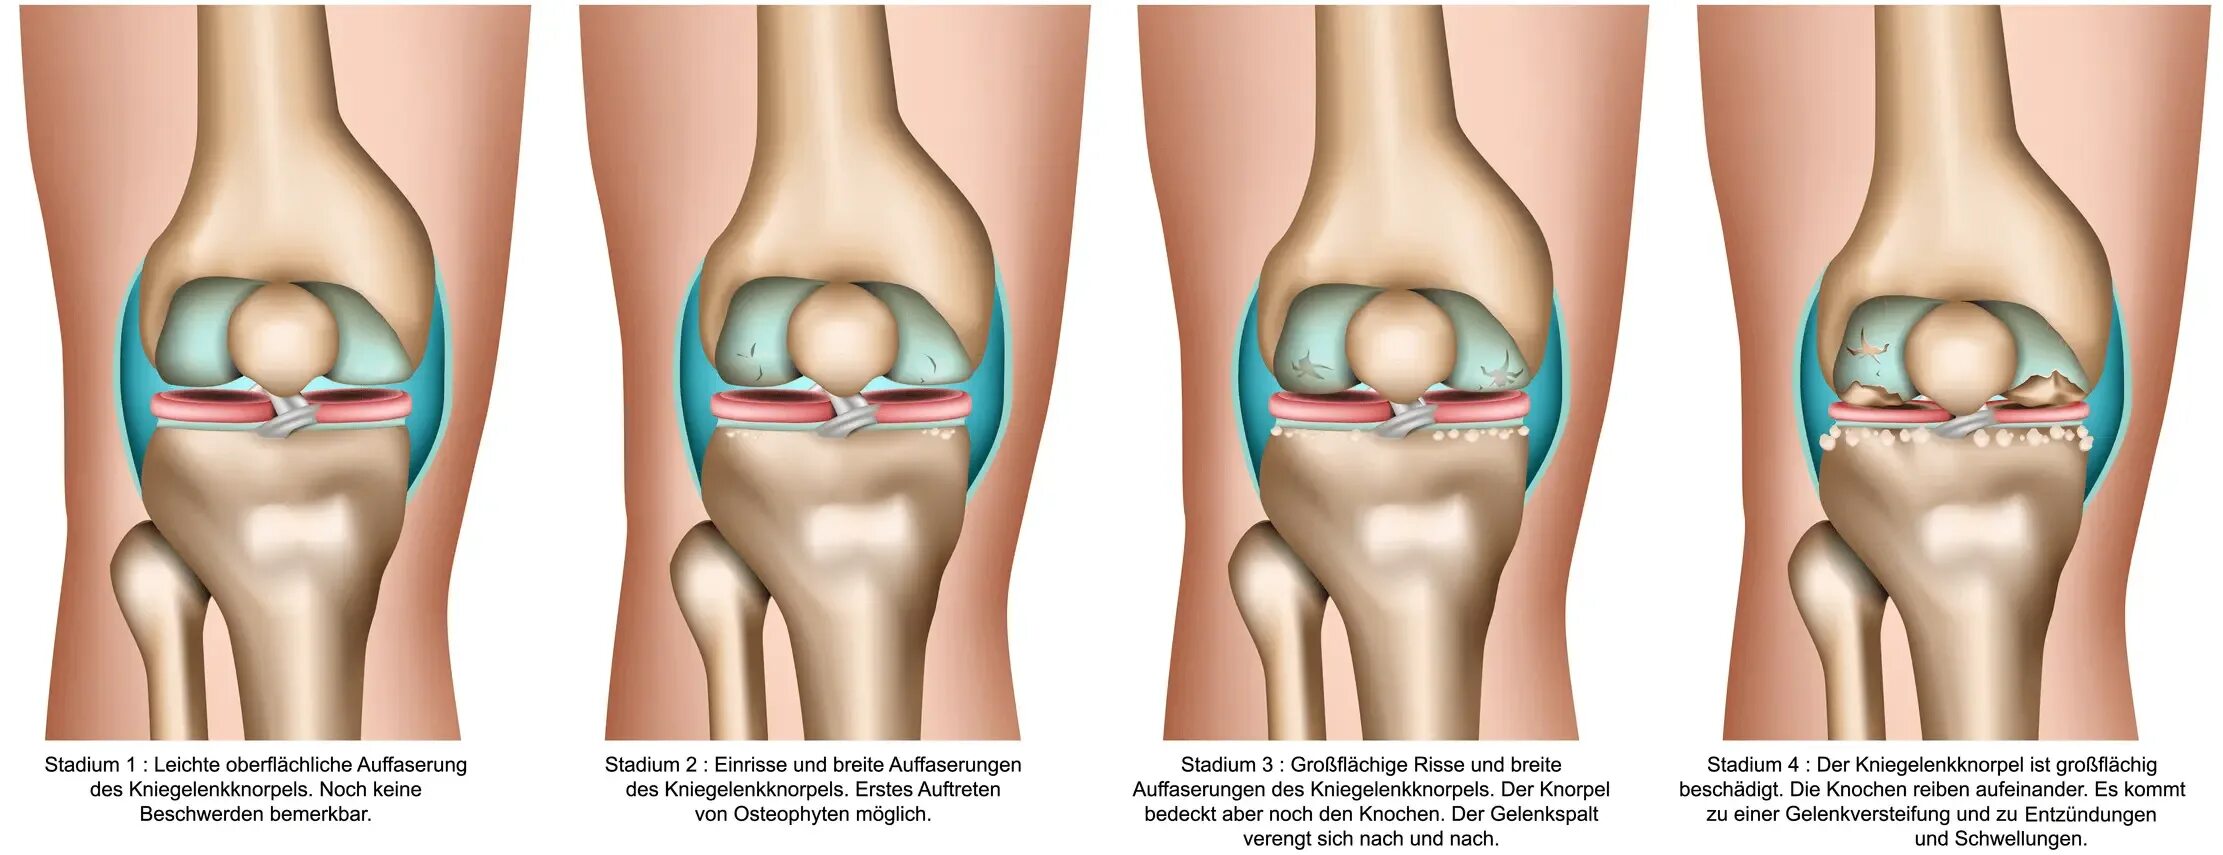

Остеоартрит 2025